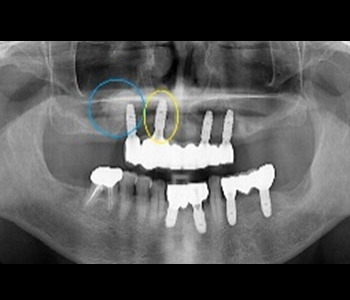

BEFORE

노란색 표시 부위는 공여부 – block bone을 채취한 곳입니다. 파란색 표시 부위는 임플란트 식립 부위로서 한 번의 마취로 어차피 임플란트 식립해야 하는 부위를 포함시켜 두 개의 수술을 완료했다는 의미입니다.